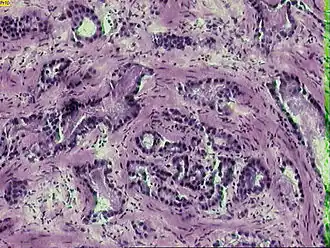

![]() Микрофотография инвазивной аденокарциномы простаты | |